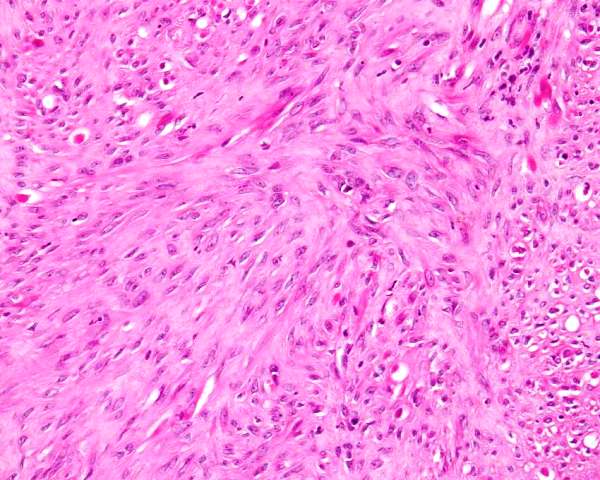

Webpathology.com: A Collection Of Surgical Pathology Images

www.webpathology.com

www.webpathology.com

uterus leiomyoma atypical bizarre webpathology pathology tumor comments